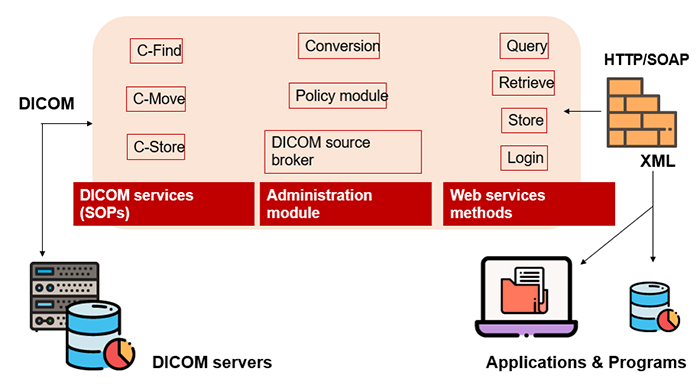

DICOM

DICOM is the international standard used to transmit, store, retrieve, print, process, and display medical imaging information. It involves the integration of image-acquisition devices, PACS, workstations, VNAs and printers from different manufacturers. DICOM is an acronym for Digital Imaging and Communications in Medicine and originated in 1983. It was developed and is maintained to meet the evolving technologies and needs of medical imaging today. It is free to download and use by institutions.

PACS

A picture archiving and communication system (PACS) is a medical imaging technology that provides economical storage and convenient access to images from multiple modalities. The universal format for PACS image storage and transfer is DICOM (Digital Imaging and Communications in Medicine). Combined with available and emerging web technology, PACS can deliver timely and efficient access to images, interpretations, and related data. PACS is used by radiology personnel to manage the workflow of patient exams.